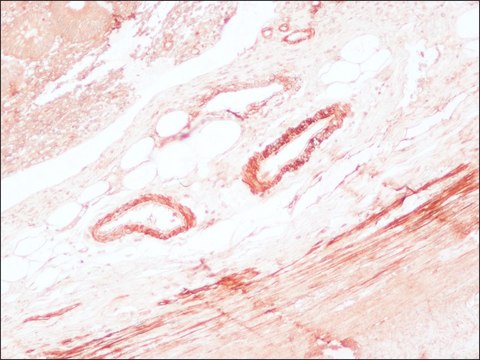

immunohistochemistry (formalin-fixed, paraffin-embedded sections): 1:100